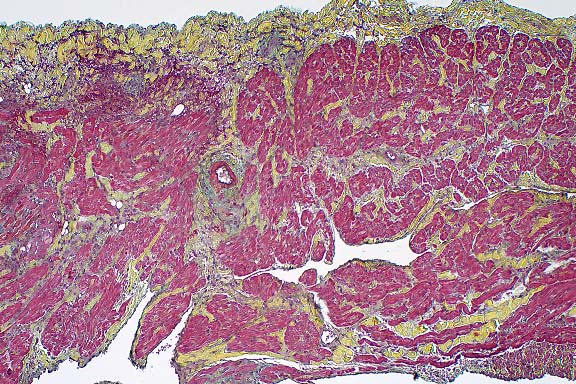

- The lung has multiple, discrete, subpleural granulomas which

each contain a single immature cestode that lacks a bladder wall.

The cestode larvae are nonsegmented and contain an invaginated

scolex. Occasional sections of the larvae show the presence of

suckers in the invaginated canal. Larvae have multiple small

lightly basophilic calcareous corpuscles. The reaction is characterized

by fibrous septal thickening, type II pneumocyte hyperplasia

and a mix of inflammatory cells consisting of eosinophils, macrophages,

plasma cells, and lymphocytes. A layer of degenerate inflammatory

cells lies adjacent to the cestodes. The pleura is thickened

by chronic pleuritis.

- Case 8-1 . Lung. The 2x view shows 3 profiles of cestode

larva surrounded by a dense inflammatory infiltrate forming a

granuloma adjacent to the pleura surface. Surrounding alveoli

have mild alveolar emphysema and thickened alveolar septa. At

40x, multiple calcarious corpuscles (blue bodies with clear halos)

are scattered within the mesenchyme of the larva. The tegument

has a thick eosinophilic, 15-20u, smooth surfaced cuticle. The

surrounding interstitium is fibrotic with moderate numbers of

infiltrating eosinophils and fewer macrophages and lymphocytes.